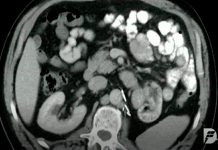

Novo tratamento do cancro renal avançado é mais eficiente

Doentes de cancro renal avançado podem beneficiar com nova terapia que combina dois medicamentos. Ensaio clínico de fase 3 mostra haver um aumento significativo de sobrevida sem progressão em comparação com o atual tratamento padrão.